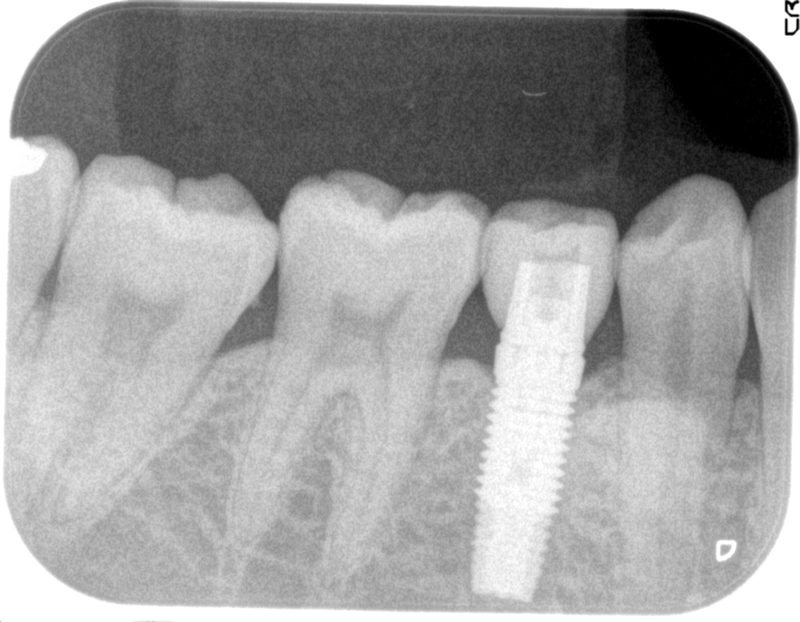

レントゲンではこのように、インプラントが骨に植え込まれたことがわかります。

なお、レントゲンではこのように見えることとなります。